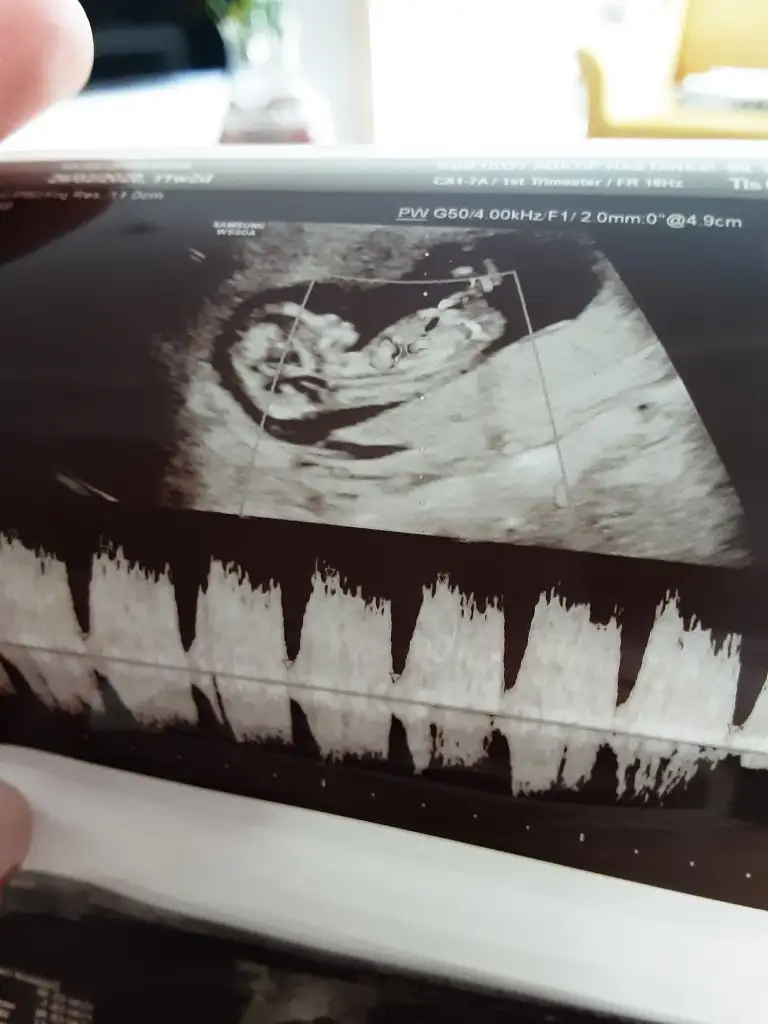

11. Haftamdayım tahmin yapar mısınız?

Ayy çok sevindim saglıkla buyusunler 😍Kaç haftalık bu usg emin değilim sanki erkek gibi 😊 anketimi oyladınmı canım